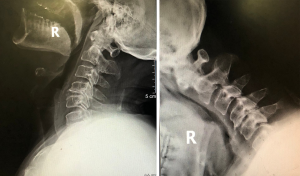

Case 1 (Figures 4 and 5 )

A 12-year-old boy with a chief complaint of neck and shoulder pain for more than 2 years presented to our hospital. The patient was neurologically intact, and the physical examination showed a limited cervical range of motion. Although the hyperflexion-extension plain film examination showed no instability, an increase in the ratio of PAOI (PAOI = ~1) and extremely small PAOI distance were observed. In addition, the patient was found to have cervical curvature changes and mild cervical disc degeneration on MRI scans. Conservative treatment was initiated.